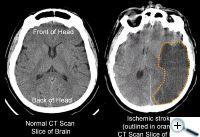

Jde o poruchu v prokrvení mozkové tkáně. Při CMP může dojít k ucpání (v 80% případů) či k prasknutí některé mozkové cévy. To má za následek poškození okolní mozkové tkáně. Ta je buď poškozena nedostatkem přívodu životně důležitého kyslíku a jde o mozkový mozkový infarkt, nebo tlakem krve proudící z prasklé cévy. Rozlišit mezi CMP z nedokrevnosti mozku a CMP vzniklou krvácením dokáže s jistotou vyšetření počítačovou tomografií (CT).